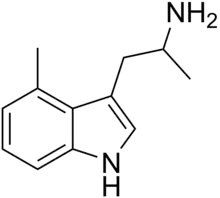

List of substituted α-alkyltryptamines

α-Alkyltryptamines are a group of substituted tryptamines which possess an alkyl group, such as a methyl or ethyl group, attached at the alpha carbon, and in most cases no substitution on the amine nitrogen.[17][18][19] α-Alkylation of tryptamine makes it much more metabolically stable and resistant to degradation by monoamine oxidase, resulting in increased potency and greatly lengthened half-life.[19] This is analogous to α-methylation of phenethylamine into amphetamine.[19]

αMT | 1-(1H-Indol-3-yl)propan-2-amine | 299-26-3 |

4-Methyl-αMT | 1-methyl-2-(4-methyl-1H-indol-3-yl)-ethylamine | 3569-29-7 |